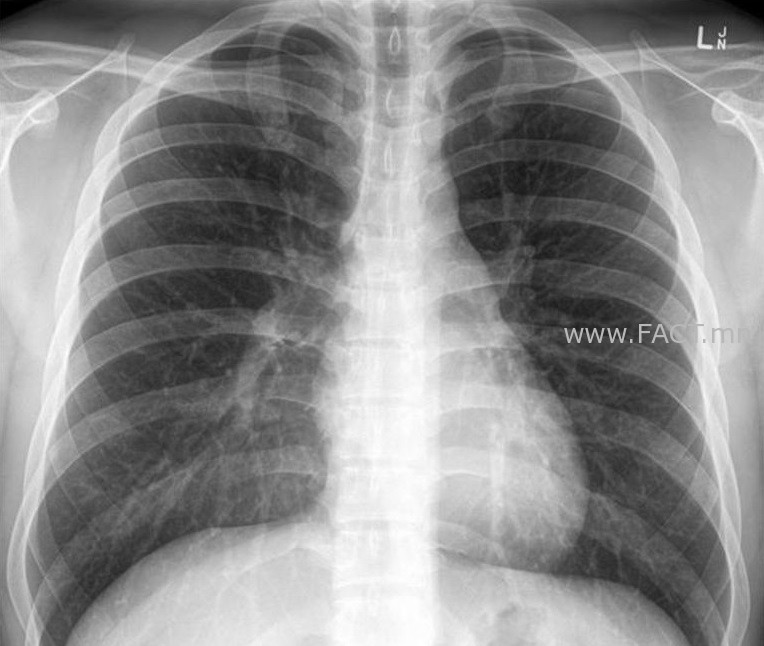

Ууушгины рентген зураг авдаг эмнэлгүүдийн ачаалал ч эрс ихэссэн байна.

Тухайлбал зураг авахуулахад 27-45 мянган төгрөг болжээ. Гэхдээ уушгиныхаа зургийг уншуулах эмч хайх гэдэг нь бас л асуудал аж. Уушгины зураг уншиж байгаа эмнэлгүүдийн ачаалал нэмэгдэхийн хэрээр үнэ нь бас багагүй нэмэгдэж 28-35 мянган төгрөгийн үнэтэй болсон байна.